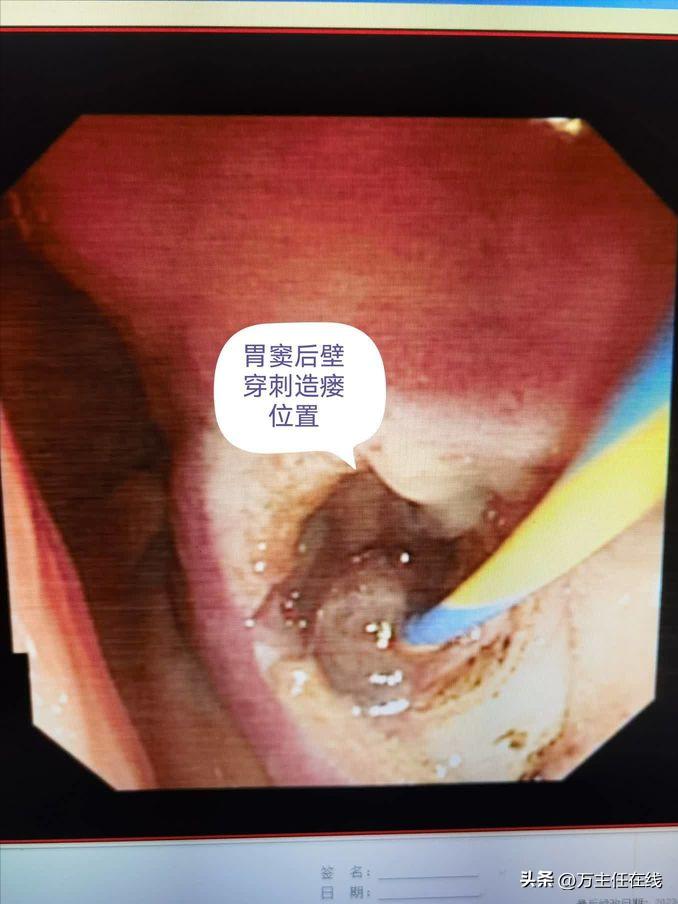

胃窦后壁穿刺点以囊肿切开刀扩大穿刺通道,并有粘液流入胃腔

有粘液流入胃腔